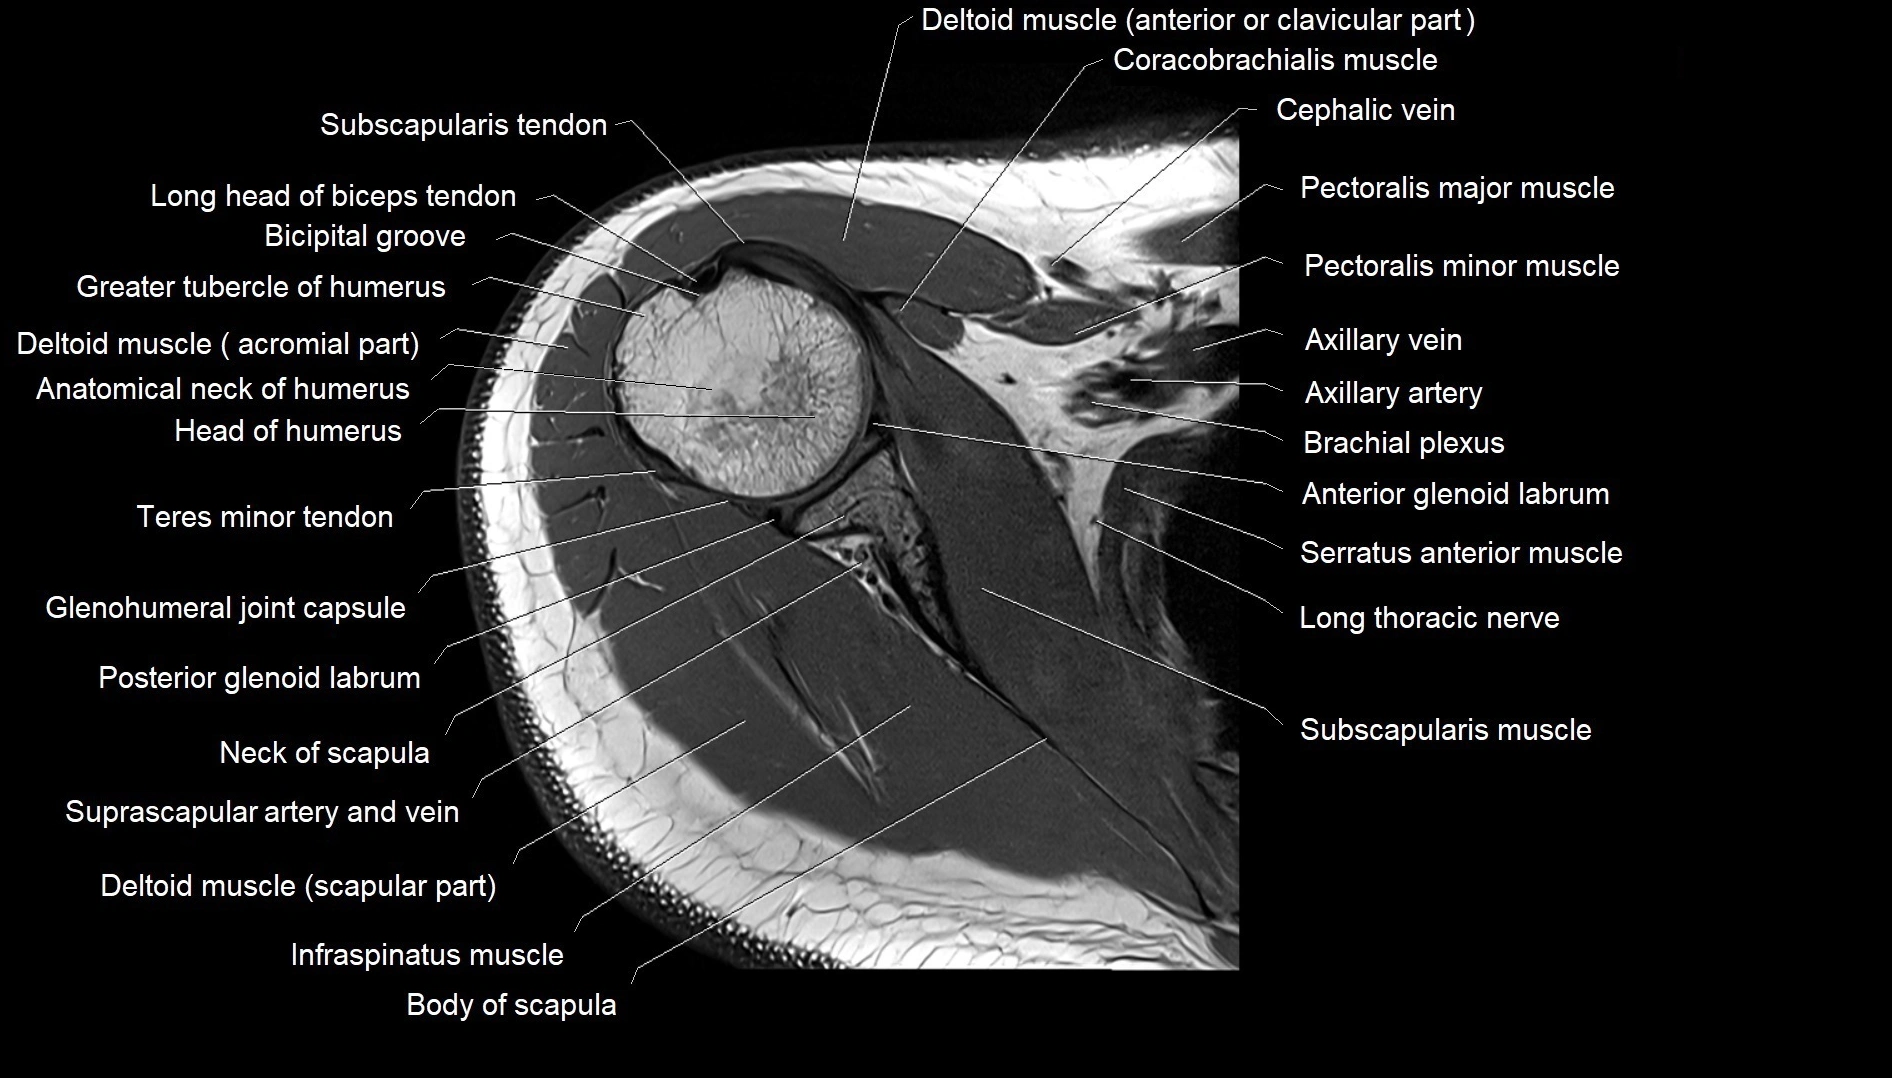

MRI images

image